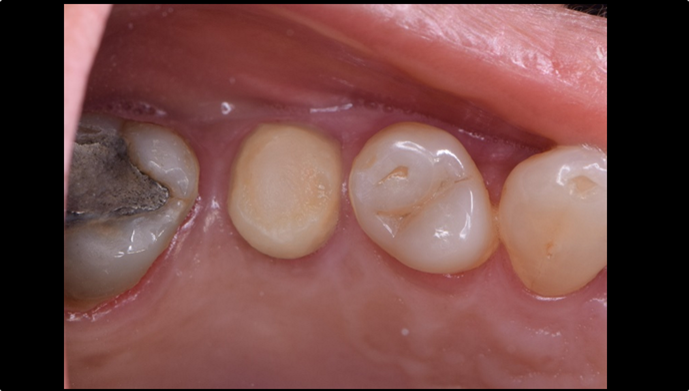

“Does guided surgery always mean flapless surgery? ”

Clinical case: R2GATE GUIDE surgery with GBR

- Courtesy of Dr. Kwang Bum Park, Korea -

Dr. Kwang Bum Park, digital guided surgery, bone regeneration, maxillary posterior, #13, #14, guided surgery, GBR, AnyRidge, i-GEN, Mega-Oss, R2GATE, R2GATE Full surgical kit

Products:

AnyRidge implant system, R2GATE Guide, R2GATE surgical kit (AnyRidge), Mega ISQ, Mega-Oss